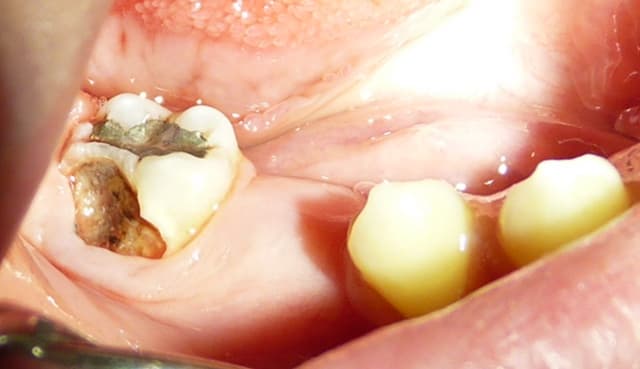

Qui ferait quoi dans le cas ci-dessous : 11 ans, patient en classe I, normodivergent, hygiène médiocre, très coopérant au fauteuil. 36 présente une carie similaire en lingual. Ces deux dents sont vitales.

P1010943 sukwth - Eugenol

Ext6 ka1zci - Eugenol

Gbazylo1 fvg1vg - Eugenol